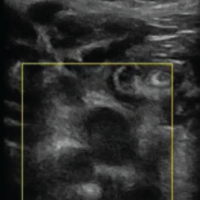

A 46-year-old right-handed female presented with severe left elbow pain for the past 1 year. The pain has progressively worsened, persisting even at rest and aggravating with movements of the forearm and wrist, such as lifting objects. There was no history of trauma or overuse of the elbow. A similar episode occurred one year ago, which was diagnosed clinically as lateral epicondylitis. Initially managed by oral naproxen 500 mg twice daily for 3 weeks, resulting in partial pain relief. This was followed by a structured physiotherapy program over 4 weeks, comprising progressive resistance exercises targeting wrist extensors, eccentric strengthening, and stretching of the extensor carpi radialis brevis. The patient reported moderate improvement in symptoms after completion of the program. However, 2 months later, pain recurred with increased intensity that was treated with a single dose of 1 ampoule of local triamcinolone acetonide injection around the lateral epicondyle. The patient experienced significant symptomatic relief within 1 week, with pain subsiding almost completely over the following fortnight. No further rehabilitation or physiotherapy was given after the injection. After 1 year, she presented with unrelenting pain for 2 weeks and rated 8 on the Visual Analog Scale (VAS), which was significantly hampering her daily activities. On physical examination of the left forearm, there was tenderness over the lateral epicondyle of the humerus and the proximal radioulnar joint. Pain exacerbated on wrist extension, and both cozen’s and varus stress tests were positive. There was restriction of flexion at the elbow joint (100°), and the Mayo elbow performance score was 60. A plain radiography of the left elbow revealed calcific deposits at the lateral epicondyle, suggestive of calcific tendinitis (Fig. 1). To evaluate soft-tissue involvement, MRI was performed, revealing proton density fat-suppressed hypointense thickening of the lateral collateral ligament (Fig. 2), further corroborating the radiographic findings.

Figure 2: Magnetic resonance image (coronal) showing proton density fat-suppressed hypointense thickening of the lateral collateral ligament.